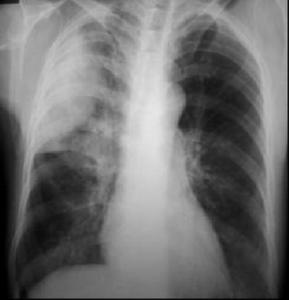

(三)X線檢查

支氣管肺炎的病因不同,因此在X線上所表現的變化既有共同點,又各有其特點。早期見肺紋理增粗,以後出現小斑片狀陰影,以雙肺下野、中內帶及心膈區居多,並可伴有肺不張或肺氣腫,斑片狀陰影亦可融合成大片,甚至波及整個節段。

1.病灶的形態

支氣管肺炎主要是肺泡內有炎性滲出,多沿支氣管蔓延而侵犯小葉、肺段或大葉。X線徵象可表現為非特異性小斑片狀肺實質浸潤陰影,以兩肺、心膈角區及中內帶較多,這種變化常見於2歲以下的嬰幼兒,小斑片病灶可部分融合在一起成為大片狀浸潤影,甚至可類似節段或大葉肺炎的形態。若病變中出現較多的小圓形病灶時,就應考慮可能有多種混合的化膿性感染存在。

2.肺不張和肺氣腫征

由於支氣管內分泌物和肺炎的滲出物阻塞,可產生部分性肺不張或肺氣腫,在小兒肺炎中肺氣腫是早期常見徵象之一,中毒症狀越重肺氣腫就越明顯,在病程中出現泡性肺氣腫及縱隔氣腫的機會也比成人多見。

3.肺間質X線征

嬰兒的肺間質組織發育好,患支氣管肺炎時,可以出現一些肺間質的X線徵象,常見兩肺中內帶紋理增多、模糊。流感病毒肺炎、麻疹病毒肺炎、百日咳桿菌肺炎所引起的肺間質炎性反應都可有這些X線徵象。

4.肺門X線征

肺門周圍局部的淋巴結大多數不腫大或僅呈現肺門陰影增深,甚至肺門周圍濕潤。

5.胸膜的X線征

胸膜改變較少,有時可出現一側或雙側胸膜炎或胸腔積液的現象。儘管各種不同病因的支氣管肺炎在X線表現上有共同點,但又不盡相同,因此,必須掌握好各種肺炎的X線表現,密切結合臨床症狀才能做出正確診斷。